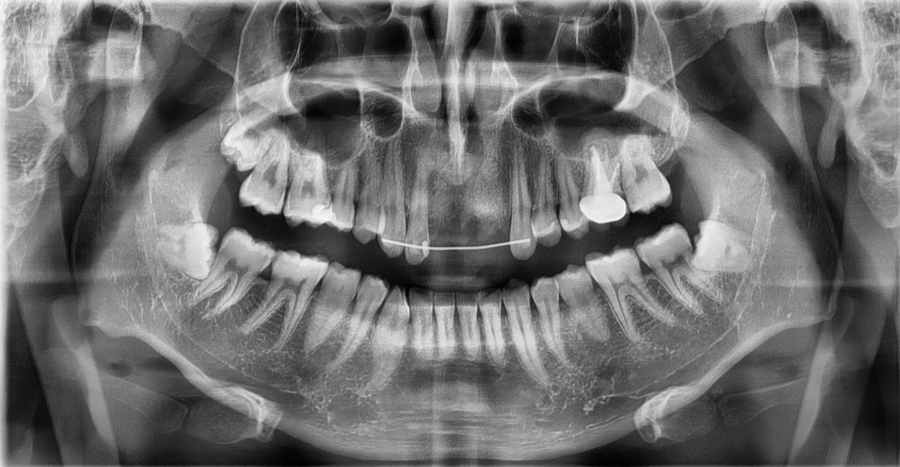

This is an X-ray of a patient who visited with a front tooth that had been completely knocked out due to the impact of a traffic accident.

This is a case in which temporary splint fixation using wire was first performed to stabilize the gums and surrounding structures supporting the teeth.